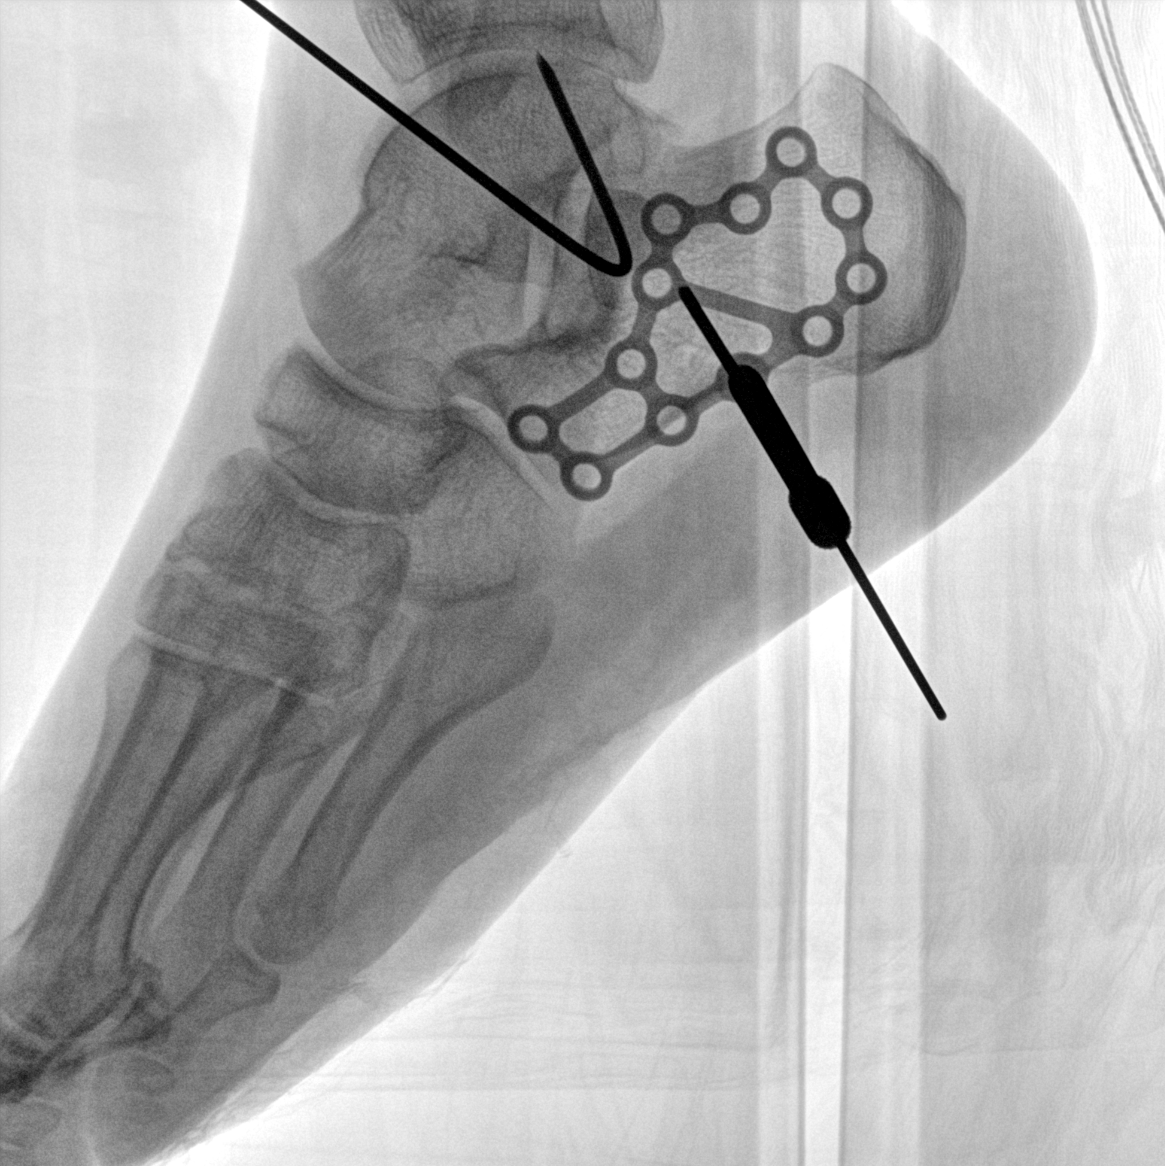

術(shù)中三維成像和橫斷面圖像提供多角度的手術(shù)診斷信息,輔助醫(yī)生進(jìn)行術(shù)中評(píng)估判斷,諸如骨折復(fù)位情況和內(nèi)植入螺釘?shù)某叽绾臀恢?,輔助手術(shù)更好地完成。

平板垂直升降運(yùn)動(dòng) 便于術(shù)中微調(diào)平板與拍攝主體的距離,更加貼近病灶體,成像范圍更大,圖像更清晰。